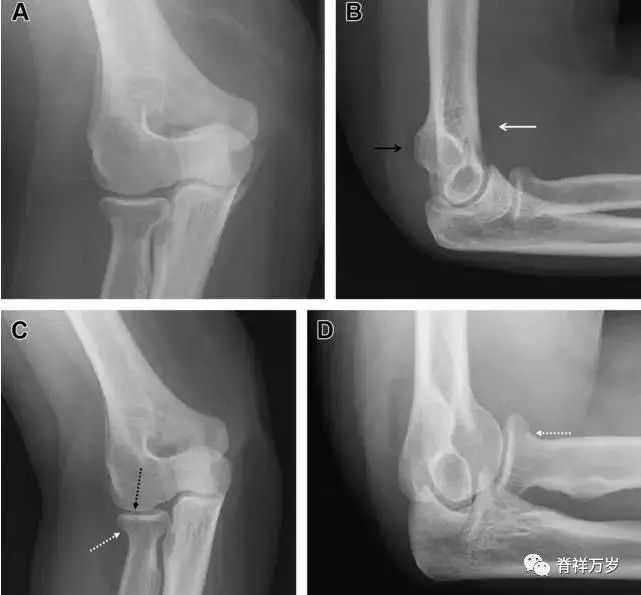

无移位的桡骨头/颈骨折

多发生于摔倒时,手掌撑地,受到轴向、外翻应力所致。常规的前后位片容易漏诊,常需加拍内斜位、外斜位、桡骨头-肱骨小头位片。后脂肪垫可见(位于鹰嘴窝内,一般不可见)和/或前脂肪垫抬高常提示骨性损伤。

图 2 桡骨头骨折。前后位(A)和侧位(B)片示后脂肪垫抬高(黑色箭头),前脂肪垫抬高(白色箭头),呈「帆船征」,其它表现正常;外斜位(C)和桡骨头–肱骨小头位(D)示桡骨头关节内骨折线(虚线黑箭头)累及桡骨颈(虚线白箭头)。